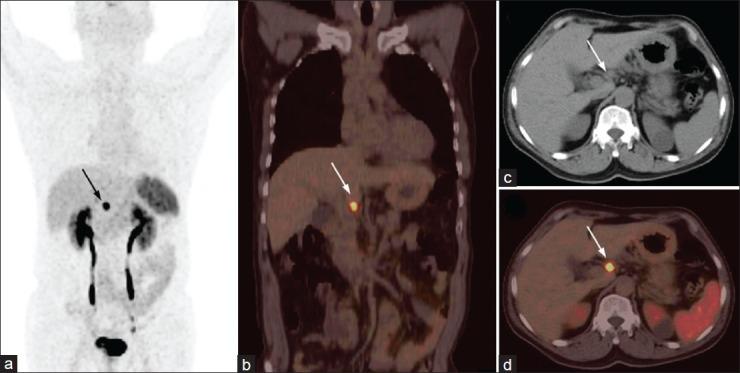

Neuroendocrine tumors (NETs) are rare neoplasms characterized by overexpression of somatostatin receptors (SSTRs). Functional imaging plays a crucial role in management of NETs. Recently, positron emission tomography/computed tomography (PET/CT) with (68)Gallium ((68)Ga)-labeled somatostatin analogues has shown excellent results for imaging of NETs and better results than conventional SSTR scintigraphy. In this review we have discussed the utility of (68)Ga-labeled somatostatin analogue PET/CT in NETs for various established and potential indications. In addition we have also shared our own experience from a tertiary care center in India.

神经内分泌肿瘤(NETs)是一种罕见的肿瘤,其特征是生长抑素受体(SSTRs)过度表达。功能成像在NETs的管理中起着至关重要的作用。最近,使用(68)镓((68)Ga)标记的生长抑素类似物的正电子发射断层扫描/计算机断层扫描(PET/CT)在NETs成像中显示出优异的结果,并且比传统的SSTR闪烁扫描结果更好。在这篇综述中,我们讨论了(68)Ga标记的生长抑素类似物PET/CT在NETs中用于各种既定和潜在适应症的效用。此外,我们还分享了我们在印度一家三级医疗中心的经验。